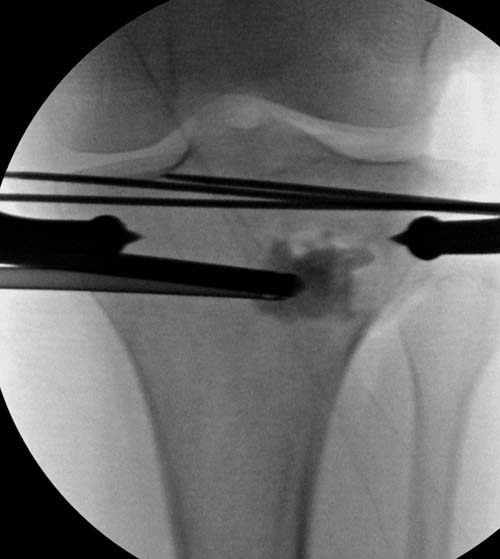

[Ortho] Импрессионный перелом латерального мыщелка левой большеберцевой кости.

Для лечения некоторых видов центральной импрессии (Schatzker III) можно

применить методику Balloon tibioplasty, которая позволяет приподнять

сустав без дополнительных доступов. Для информации здесь недавний

пример, дефект заполнен жидкой формой композитного материала PRO-DENSE: